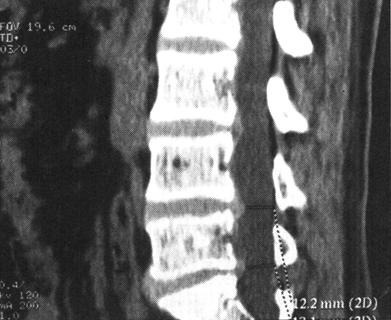

CT在脊柱脊髓损伤中应用很广泛,横断面成像是诊断脊椎骨结构创伤的主要手段,它可显示X线平片不易显示的细微骨折和小关节脱位,并能够很好地显示骨性椎管的情况,可为评价脊髓受压情况提供重要的影像学信息。螺旋CT扫描技术可对患者进行快速连续多部位成像,并支持多平面及三维成像。因而CT扫描对理解脊柱复杂解剖部位,发现细微病变有十分重要的临床意义(图7-4至图7-6)。甚至明显侧弯变形脊柱的冠状面重建亦可通过严格按照脊柱弯曲度改进的软件而获得。单纯轴位扫描很容易漏诊与CT断层面平行的骨折,例如,发生在齿突基部和胸腰水平的创伤,在横断位扫描中不能显示横断水平的骨折线,但在高质量的冠状、矢状和三维的重建图像中显示良好(图7-7至图7-10)。

图7-7、图7-8 多排螺旋CT2D重建,显示C2齿状突基底部骨折